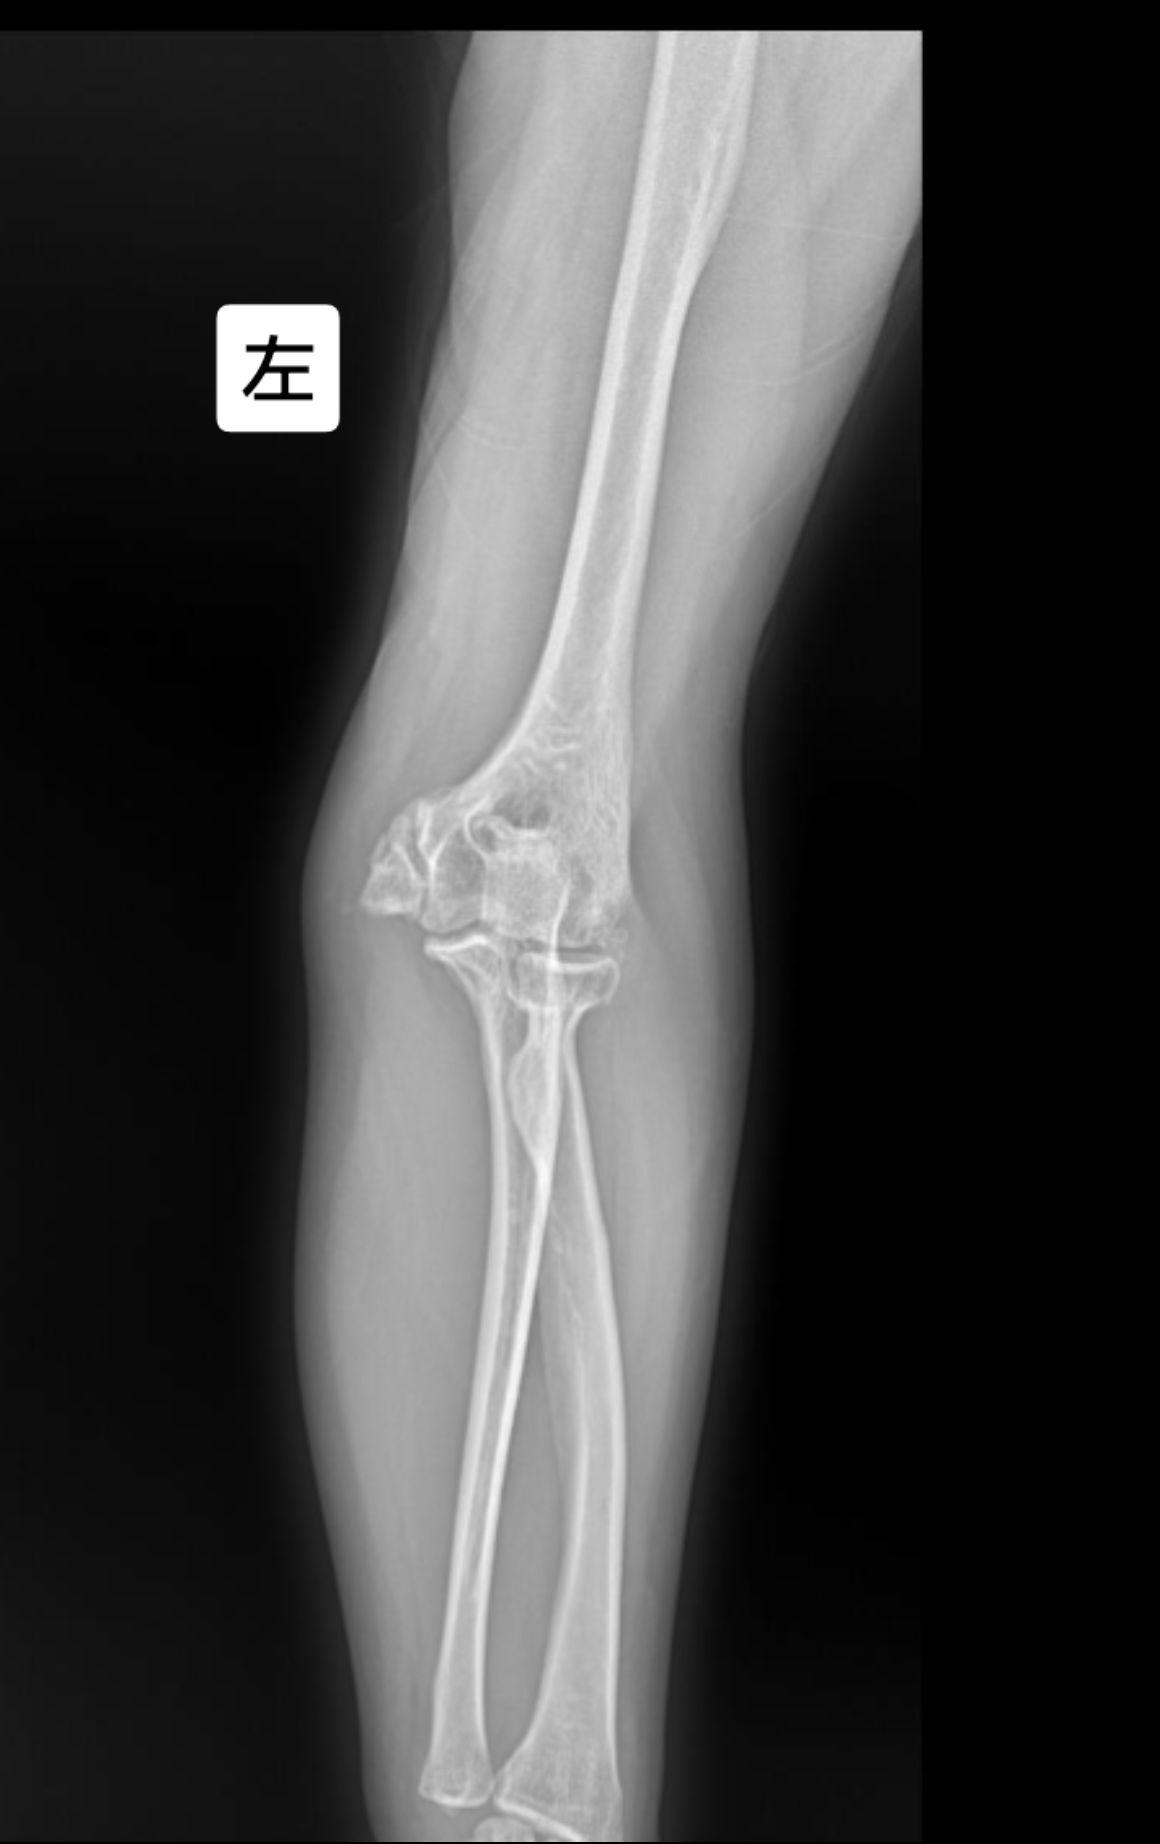

左肘关节外伤就诊